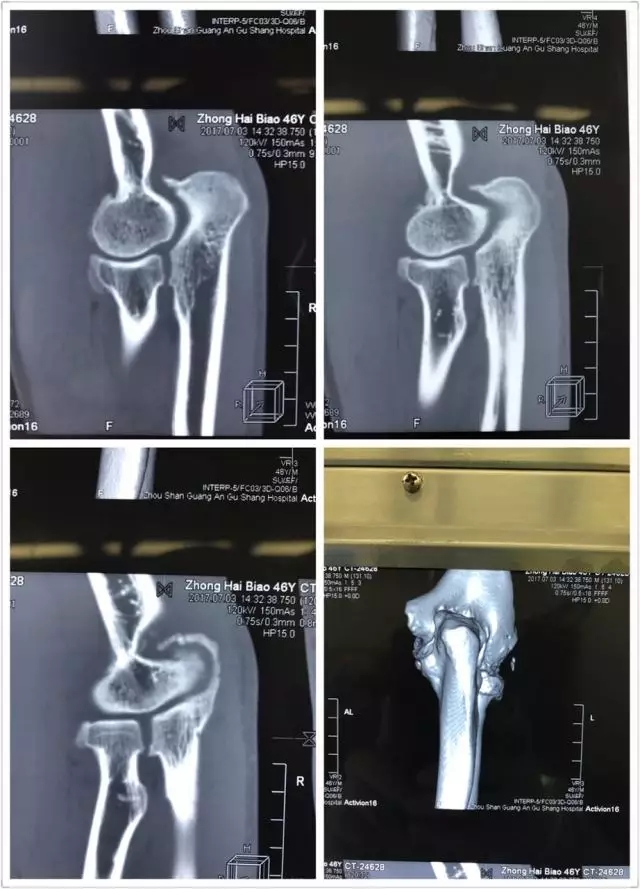

患者钟某某,男,46岁,渔民,由于一年前的一次手肘部外伤,在受伤后一直隐隐作痛,加上日常生活中劳作过度,所以手臂一直处在“过劳”的状态。

近几个月,持续的疼痛让这位轻易不言痛的大男人也忍无可忍,有时候某一个动作所致,会疼得出汗,也有过很多个夜晚无法入眠的疼痛时刻。尝试过各种止痛药、膏药,都无法根除疾病,并逐渐出现肘关节不能伸直。

于是他慕名来到舟山广安医院危立军副院长处就诊,诊断为肘关节内游离体,肘关节伸直功能障碍。

舟山广安医院关节镜与运动医学科罗军主任带领其王鹏医师及团队成员采用国际上先进的肘关节镜技术,为这位患者施行肘关节镜下游离体取出,骨赘清除,尺骨鹰嘴窝成形术,术后患者症状明显好转,折磨了一年多的疼痛消失了,脸上重新露出了笑容。